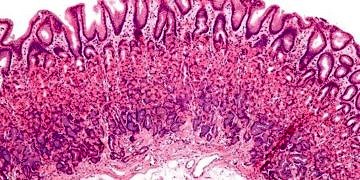

Gastroözofageal reflü; mide içeriğinin özofagusa doğru geri kaçmasıdır. Gastroözofageal reflü hastalığı; özofagusa geri kaçan mide içeriğinin semptomlara ve özofagusta hasara...

DevamıKronik peptik ülser toplum sağlığını ilgilendiren hastalıkların başında. Dünyanın her yerinde ve her ırkta. Fakir ülkelerde daha sık. Batıda prevalans % 1.5-2.5. Her yaşta görülebilme. Otopsilerde erkeklerde...